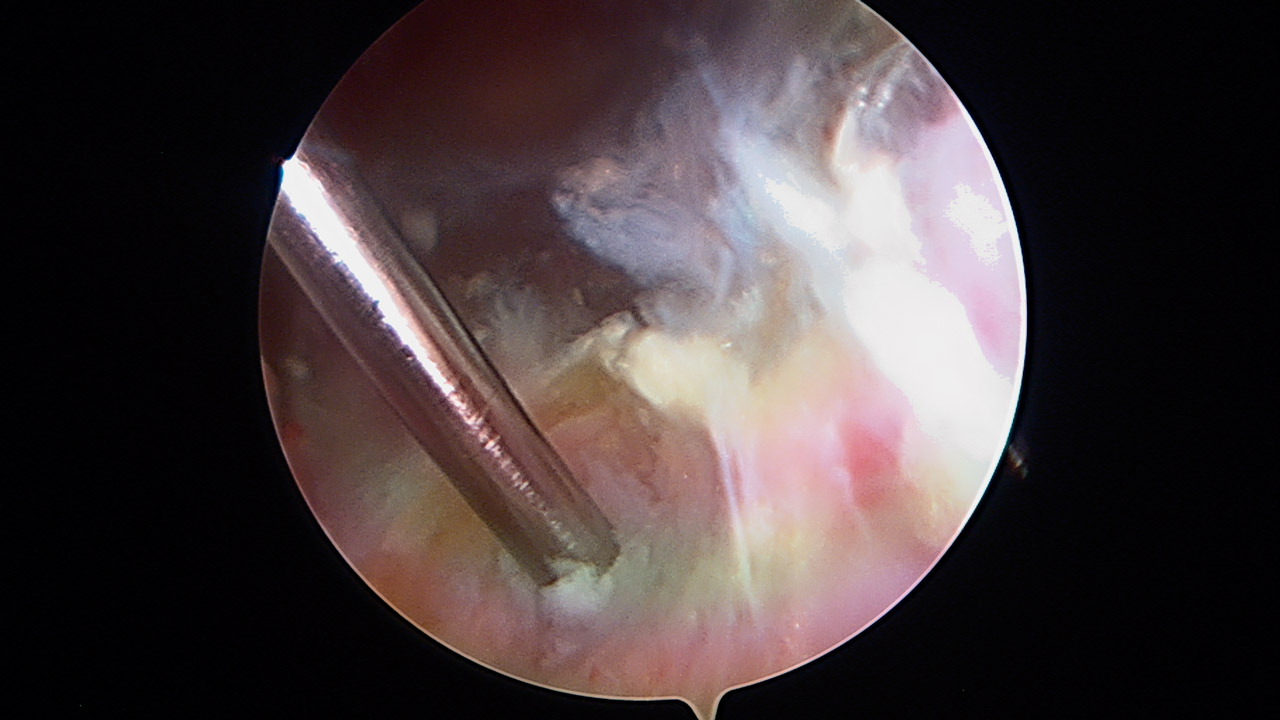

Paso 2: túnel humeral

Cambiamos la visión al portal anterior E, buscando la cara anterior humeral. La posición del brazo se mantiene neutra, sin tracción. Realizamos un portal inferior J con visión directa, que servirá para realizar el túnel humeral. Se diseca el espacio entre la porción larga del bíceps (PLB), el pectoral mayor y el dorsal ancho (Figura 5). Se debe tener precaución con el nervio radial que discurre sobre el dorsal ancho. El punto isométrico de fijación de la plastia se encuentra 1 cm medial a la corredera bicipital y craneal al dorsal ancho. En este punto hay que tener precaución con las “tres hermanas” en la cara inferior del subescapular, ya que el punto de fijación es inferior a las mismas, entre el subescapular y el dorsal ancho . Apoyada en una guía de anclaje Iconix® 2,3, introducimos una aguja de Beath con dirección superior hacia el ángulo posterior del acromion, evitando la posible lesión del nervio axilar en el cuello humeral (Figuras 6 y 7). Se perfora la cortical humeral con un grosor de 7 mm hasta 25 mm de profundidad y se deja una sutura que servirá de transporte del injerto.